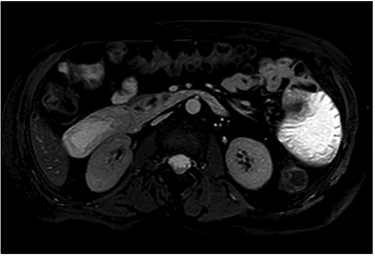

After clinical evaluation, the patient underwent computed tomography (CT) of abdomen and pelvis with IV contrast, which revealed fluid-filled esophagus, dilated stomach and first part of the small intestine with a transition point in the mid jejunum (Fig. 1). Her proximal small bowel, stomach and esophagus were significantly distended. She was subsequently decompressed with a nasogastric tube. For further delineation of this transition point, a magnetic resonance imaging (MRI) was performed, which confirmed a narrowed lumen secondary to an intrinsic mass of the jejunum (Fig. 2). Later, she underwent exploratory laparotomy with an evident transition point found at 30 cm from the ligament of Treitz (LT) (Fig. 3). We performed a partial small bowel resection and side-to-side stapled anastomosis. The rest of the bowel appeared healthy; there was no evidence of serosal involvement or extension to surrounding loops of bowel. Multiple enlarged lymph nodes were identified in the mesentery.